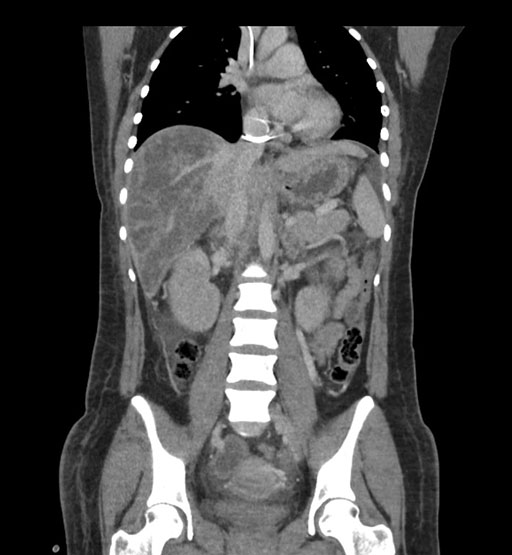

Coronal Arterial

Coronal Venous